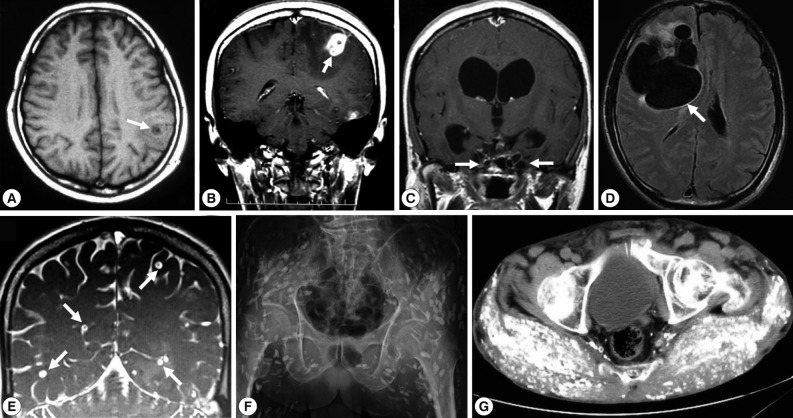

Of these 66 cases, 54 (66.7%) were NCC; NCC with multiple cysts (28/54, 51.9%; Fig. 1E) was more frequent than NCC with a solitary cyst (13/54, 33.5%; Fig. 1A, B and Fig. 2A, B, E). Between 1990 and 2011, total 17 cases of SCC were reported as cases 4 [41], 16-17 [42], 24 [43], 26 [7], 28 [9], 29 [10], 34 [16], 35 [17], 44 [27,28], 45 [29], 52 [36], 56, 63, 64, 65, and 66. Two of them were systemic intramuscular cysticercosis with numerous calcified cysts; cases 44 [27,28] and 52 [36] (Fig. 1F, G; Fig. 2D, F). Very rarely, intramedullary cysticercosis in case 5 [44] and ocular cysticercosis in cases 11 [45], 36 [18], 43 [26], and 58 [38] have also been reported. Ten cases of NCC with either SCC or ocular cysticercosis were reported in cases 16-17 [42], 26 [7], 29 [10], 35 [17], 43 [26], 45 [29], 56 , 64, and 65 (Table 1). More interestingly, dual infection of cysticercosis and taeniasis was observed in 4 cases; 29 [17], 58 [51], 60, and 65 (Table 1). Furthermore, the adult tapeworm in case 41 was observed in the small intestine using capsule endoscopy to confirm the presence of the adult worm (Table 2).

In SCC, X-ray examinations have revealed the presence of rod-like, scattered, calcified lesions in the soft tissues of the extremities (Fig. 1F, G; Fig. 2D, F). These calcified cysts have histopathologically been confirmed to be T. solium in cases 16-17 [42], 26 [7], 52 [36], and 44 [27,28] (Fig. 2A, C, E).

Two types of T. solium cysticercus, cellulose- and racemose-types, are known to exist. The cellulose-type cysticercus is characterized by a single bladder measuring 3 to 18 mm in diameter with an invaginated scolex and primarily found in the cerebral parenchyma and musculature. The racemose-type presents as large multilobulated cystic lesions lacking a scolex and appears to prefer the cisternal and ventricular systems or subarachnoid space [2]. Indeed, the racemose-type cysticercus is frequently found in the subarachnoidal spaces as multilobulated lesions (Fig. 1C, D). Although cysticercosis due to racemose-type T. solium cysticercus is relatively rare, 8 cases have been documented in Japan in cases 8 [50,51], 15 [52], 18 [53], 19 [54], 39 [21], 50 [34], 61, and 62 [40] (Table 1; Fig. 1C, D; Fig. 2C). Of these, mitochondrial DNA analysis using histopathologic sections revealed that etiologic T. solium was the Asian genotype in 3 cases, 50 [32], 61, and 62 [40], and American/African genotype in case 50 [34] (Table 1). The racemose-type cysticercus is considered to be an aberrant, multilobular, non-viable T. solium cysticercus, possibly the degenerated form of a cysticercus in the basal subarachnoid space. Molecular analysis using formalin-fixed and paraffin-embedded histopathologic specimens has proved that the racemose-type cysticercus is T. solium in cases 50 [34], 61, and 62 [40].

Most of the cysticercosis cases in Japan are imported cases, meaning that the patients either lived in or visited countries where cysticercosis and taeniasis are still endemic, and where they are presumed to have been exposed to T. solium eggs. However, 13 cases have suggested that infection occurred within Japan (cases 1 [55], 8 [50,51], 10 [56], 12 [57], 20 [54], 21 [58], 22 [59], 23 [60], 28 [9], 40 [22], 52 [36], 53, and 62 [40]. NCC was diagnosed by imaging findings (Fig. 1), serology, histopathology (Fig. 2A, C, D, E), and molecular analysis.

Imaging findings of selected cysticercosis cases. (A) plain CT image showing a solitary lesion at the left occipitoparietal area (case 48 [32], courtesy of Prof. H. Matsuoka). (B) MRI showing one of multiple cystic lesions in the left frontal and temporal lobes (case 49 [33]). (C) MRI showing a rasemose-type lesion at the basal cistern (case 50 [34], courtesy of Dr. T. Oda). (D) MRI FLAIR findings showing a giant and multilobulated mass in the subarachnoidal spaces of the right frontal lobe (case 62 [40], courtesy of Dr. S. Shiiki). (E) Cisterography showing multiple cysts in the brain (case 60, courtesy of Prof. A. Chiba). (F) X-ray findings showing typical rice grain calcifications in the muscles of buttocks and lower extremity (case 44 [27, 28], courtesy of Dr. T. Nagase). (G) CT findings showing numerous calcified cysts in muscles of the of the buttocks (case 52 [36], courtesy of Dr. M. Tsuda).

Fig. 1 Imaging findings of selected cysticercosis cases. (A) plain CT image showing a solitary lesion at the left occipitoparietal area (case 48 [32], courtesy of Prof. H. Matsuoka). (B) MRI showing one of multiple cystic lesions in the left frontal and temporal lobes (case 49 [33]). (C) MRI showing a rasemose-type lesion at the basal cistern (case 50 [34], courtesy of Dr. T. Oda). (D) MRI FLAIR findings showing a giant and multilobulated mass in the subarachnoidal spaces of the right frontal lobe (case 62 [40], courtesy of Dr. S. Shiiki). (E) Cisterography showing multiple cysts in the brain (case 60, courtesy of Prof. A. Chiba). (F) X-ray findings showing typical rice grain calcifications in the muscles of buttocks and lower extremity (case 44 [27, 28], courtesy of Dr. T. Nagase). (G) CT findings showing numerous calcified cysts in muscles of the of the buttocks (case 52 [36], courtesy of Dr. M. Tsuda).